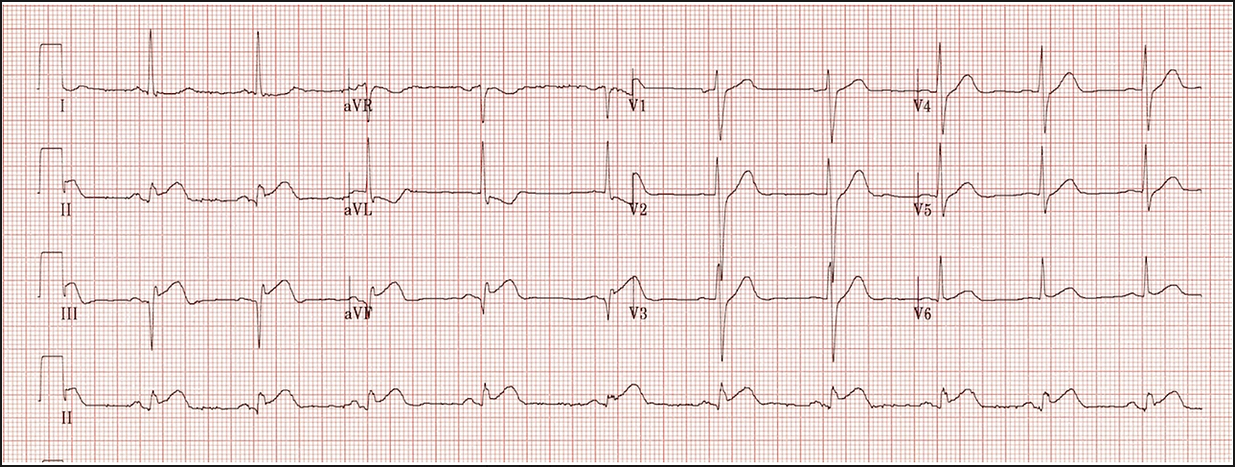

NSTEMI and Ischaemia:

This is an ECG of an NSTEMI or unstable angina. In lots of the leads ST segment depression can be seen which suggests ischaemia.

This can progress to a STEMI where ST elevation can be seen as well as other features like T-wave inversion